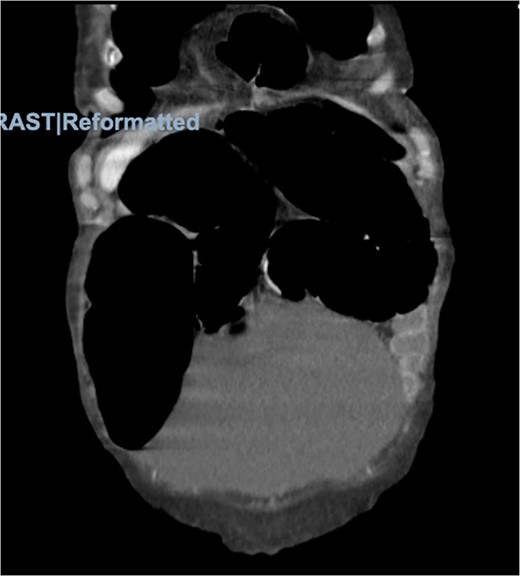

Physical examination was significant for right upper quadrant and epigastric tenderness with a mildly distended abdomen. On admission, the patient had a leukocytosis of 16.2. Imaging included computed tomography (CT) of the abdomen and pelvis showing the obstruction of the colon suspected because of a loop of colon herniated into the lower anterior chest, between the lower aspect of the sternum and the left heart border with mild mass-effect on the heart (Figs 2 and 3).

Morgagni hernia seen on CT abdomen and pelvis with contrast (sagittal view).